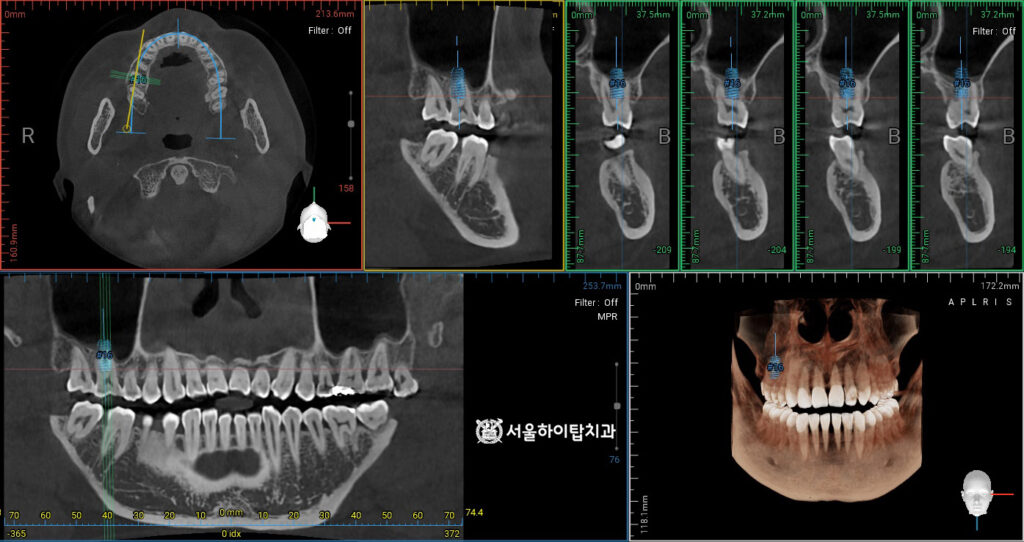

2. 정밀한 CT 검진

앞서 동암 치과 에서 말씀드린 것처럼,

염증은 다행히 현재 치근 끝까지

진행되지 않은 상태입니다.

따라서 신경치료를 통해, 향후 염증이

더 넓은 범위로 퍼지는 것을 사전에

예방할 수 있습니다.

내부의 감염된 치수를 완전히 제거한 후,

전용 충전재로 뿌리 끝까지 채워주기 때문에

치근단까지 확산되는 것을 방지할 수 있습니다.

다만 뿌리까지 이어진 fracture line은

그 상태로 오래 유지되기 어렵습니다.

그 이유는, 씹는 힘 등

저작력이 지속적으로 가해지면서

치근이 미세하게 흔들리기 때문입니다.

또한 내부 치수가 염증을 일으키면

주변 치주조직과 치근단에 압박과 자극이 생겨

파절선이 점차 확장되거나 치아 구조가 약해져

더 이상 안정적으로 유지되지 않습니다.

즉, 동암 치과 에서 쉽게 말씀드리자면,

장기적인 안정성이 부족한 상태인 셈입니다.

따라서, 이런 경우에는 위 사진과 같이

CT 촬영을 통해 치아 및 주변 구조를

정밀하게 관찰한 후,

임플란트가 식립될 위치,

뼈의 높이와 두께, 상악동과의 거리 등을

파악하는 것이 매우 중요합니다.